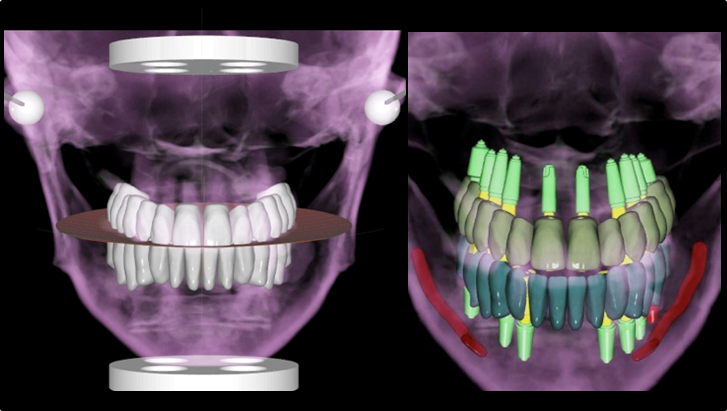

Effective R2STUDIO in complex tooth positioning

- Courtesy of Dr. Jong Cheol Kim, Korea